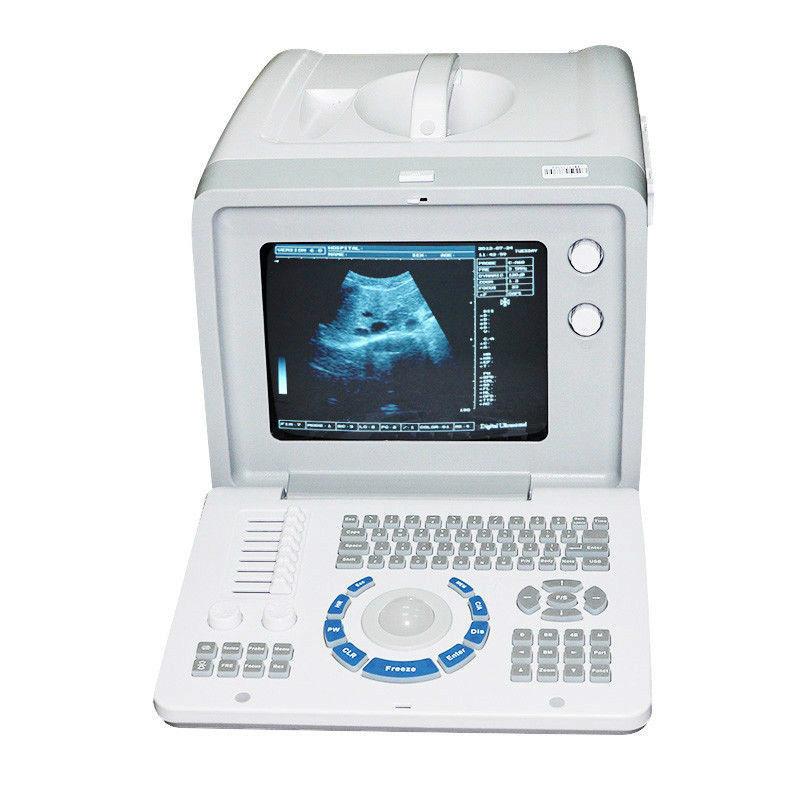

The Ultrasound Scanner is a state-of-the-art device designed for comprehensive pregnancy imaging. It features both convex and transvaginal probes, allowing healthcare professionals to obtain detailed images of the fetus and surrounding structures. This dual-probe system enhances diagnostic accuracy, making it easier to monitor the health of the unborn child. Expecting mothers benefit from these advanced imaging techniques, enabling early detection of potential complications.

User-Friendly Interface and USB Storage

This ultrasound machine is not only powerful but also user-friendly. It offers an intuitive interface, making it simple for healthcare providers to operate. Furthermore, the device includes USB storage, allowing images and data to be easily saved and shared. This feature is crucial for collaboration among healthcare teams, so they can provide the best care possible. Also, because it provides high-quality images, professionals can make informed decisions regarding patient management.

Improving Diagnostic Accuracy and Patient Care

The importance of the Ultrasound Scanner in modern medicine cannot be overstated. By combining advanced technology with ease of use, this tool significantly improves diagnostic accuracy. As a result, healthcare professionals can identify any abnormalities earlier, leading to timely interventions. Additionally, the profound impact on patient care is evident, as clearer images and better diagnostics translate to enhanced outcomes for both mothers and their babies.